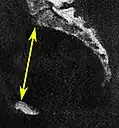

The diameters or conjugates of the pelvis are measured at the pelvic inlet and outlet and as oblique diameters.

Name Description Average measurement in female

Anteroposterior or conjugate diameter or conjugata vera Extends from the upper margin of the pubic symphysis to the sacrococcygeal joint; about 110 mm.

Transverse diameter Extends across the greatest width of the superior aperture, from the middle of the brim on one side to the same point on the opposite; about 135 mm.

Oblique diameter Extends from the iliopectineal eminence of one side to the sacroiliac articulation of the opposite side; about 125 mm.

Anatomical conjugate Extends from the pubic symphysis to the promontory; about 120 mm.

Diagonal conjugate Extends from lower margin of the pubic symphysis to the sacral promontory; about 130 mm.

Straight conjugate Extends from the lower border of the pubic symphysis to the tip of coccyx. The coccyx can bend posteriorly and expand the diameter with 25 mm; about 95 mm (+ 25 mm).

Median conjugate Extends from the lower border of the pubic symphysis to the lower border of the sacrum; about 115 mm.